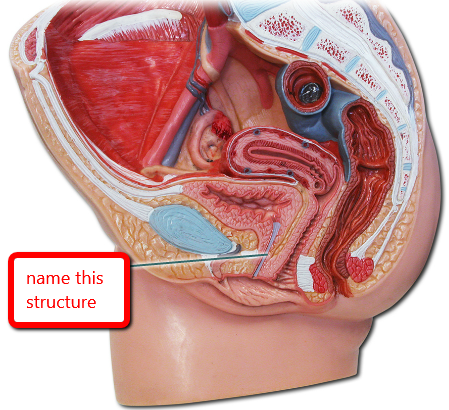

Cervix

Clitoris

Endometrium

Labia majora/minora

Myometrium

Overian ligament

Ovary

Perimetrium

Prepuce (=clitoral hood)

Round ligament (of uterus)

Urinary Bladder (female)

Uterine (=fallopian) tube

Uterus

Vagina

Vaginal orifice

Vestibule (of vulva)